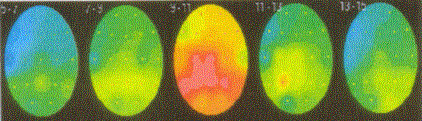

Quantitative Electroencephalograph (QEEG) is the measurement, using digital technology, of electrical patterns at the surface of the scalp which primarily reflect cortical activity or "brainwaves". A multi-electrode recording of brain wave activity is recorded and converted into numbers by a computer. These numbers are then statistically analysed and can be converted into a colour map of brain functioning.

* Coloured Dynamic Brain Map

The coloured dynamic brain map generated by a computer makes it easy for clients/patients to visualise the problems which are being explained. Thus it facilitates communication and improves the client's (and family's) understanding of their conditions.

The SKILTM Topometric QEEG provides information on brain functioning and its impact on cognition and learning. Computerised EEG results are compared to age-related norms of the QEEG database providing information about whether the client has a deviation in QEEG functioning which varies significantly from the norm. It indicates what locations, the amplitude and frequency of waves of interest, and under what conditions the abnormality manifests itself. Advanced artifact removal, time of day correction, multiple data and statistical displays, and state comparison analysis differentiate the SKILTM from other QEEG systems.

The information is visually summarised in five graphical displays: topographic maps, spectral plots, topometric distributions, covariation maps and tables. A written report follows ten days to a fortnight later.